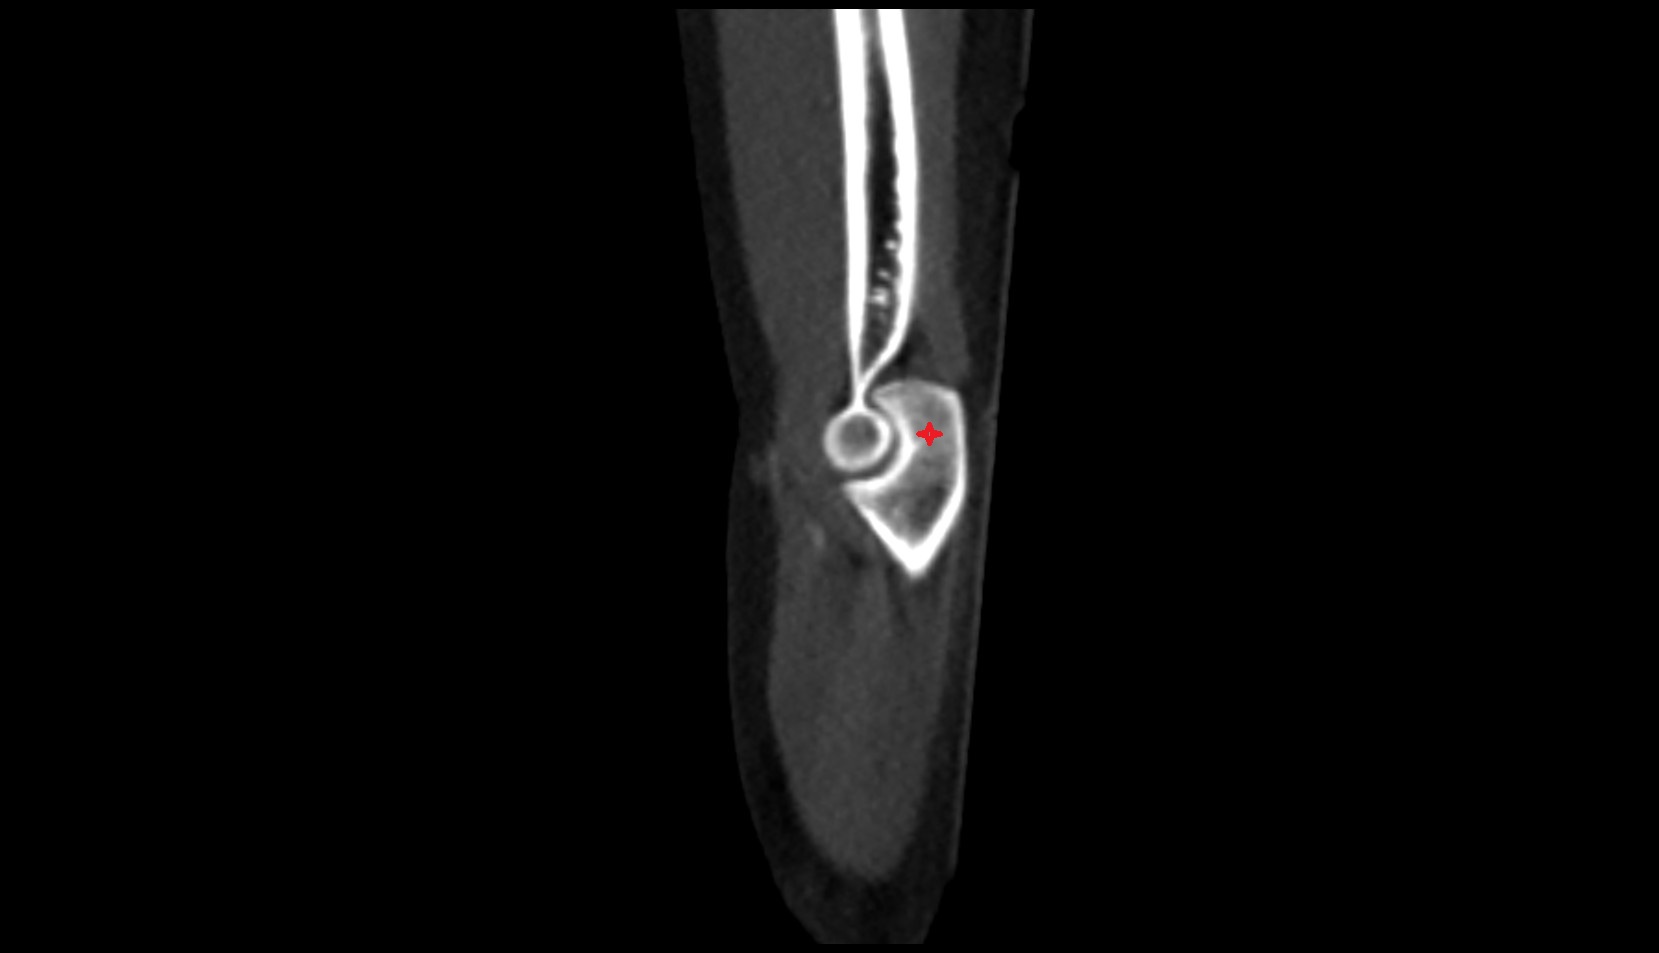

- Elbow joint

- Olecranon

- Coronoid process of ulna

- Capitulum of humerus

- Trochlea of humerus

- Head of radius

- Neck of radius

- Trochlear notch of ulna

- Coronoid fossa

- Humeroulnar joint

- Humeroradial joint

- Proximal radioulnar joint

- Joint capsule of elbow